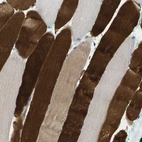

Immunohistochemical staining of human skeletal muscle shows strong cytoplasmic positivity in myocytes.